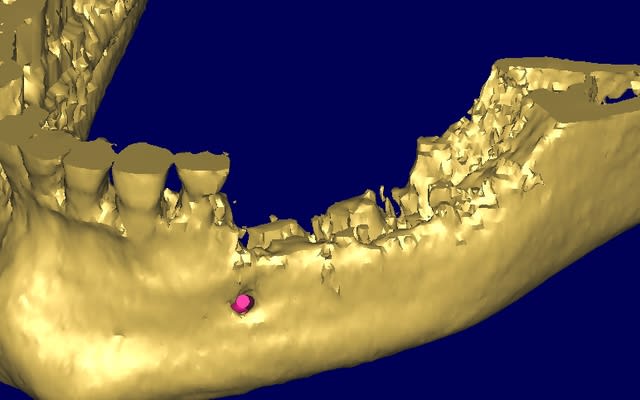

le cas n'est déjà pas facile...

il faut explanter tous le secteur 3 et 4

mais quid de la gestion osseuse ?

pour la gestion osseuse, je pensais utiliser des mesch titane et comblement avec os humain.